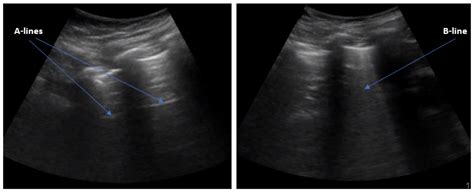

In the context of lung sonography, B Lines Ultrasound patterns are defined as discrete, laser-like vertical hyper-echoic reverberation artifacts. They arise from the pleural line and extend to the edge of the screen, moving in synchrony with lung sliding. Unlike A-lines, which represent normal horizontal reverberations caused by air-tissue interfaces, B-lines signify that the subpleural interlobular septa are thickened by fluid, cells, or fibrous tissue.

When these septa become edematous or infiltrated, they create an acoustic impedance mismatch that traps the ultrasound beam, resulting in the characteristic vertical "comet tail" appearance. Because they move with the visceral pleura, their presence is a highly sensitive marker for the loss of lung aeration.

The primary clinical value of identifying B Lines Ultrasound patterns lies in their ability to rule in or rule out interstitial syndromes. In an emergency setting, these findings are often used as a bedside tool to differentiate acute heart failure from chronic obstructive pulmonary disease (COPD) or asthma.

⚠️ Note: Always interpret B-lines within the broader clinical context. A single B-line is often considered a normal finding, while three or more in a single view are considered pathological.